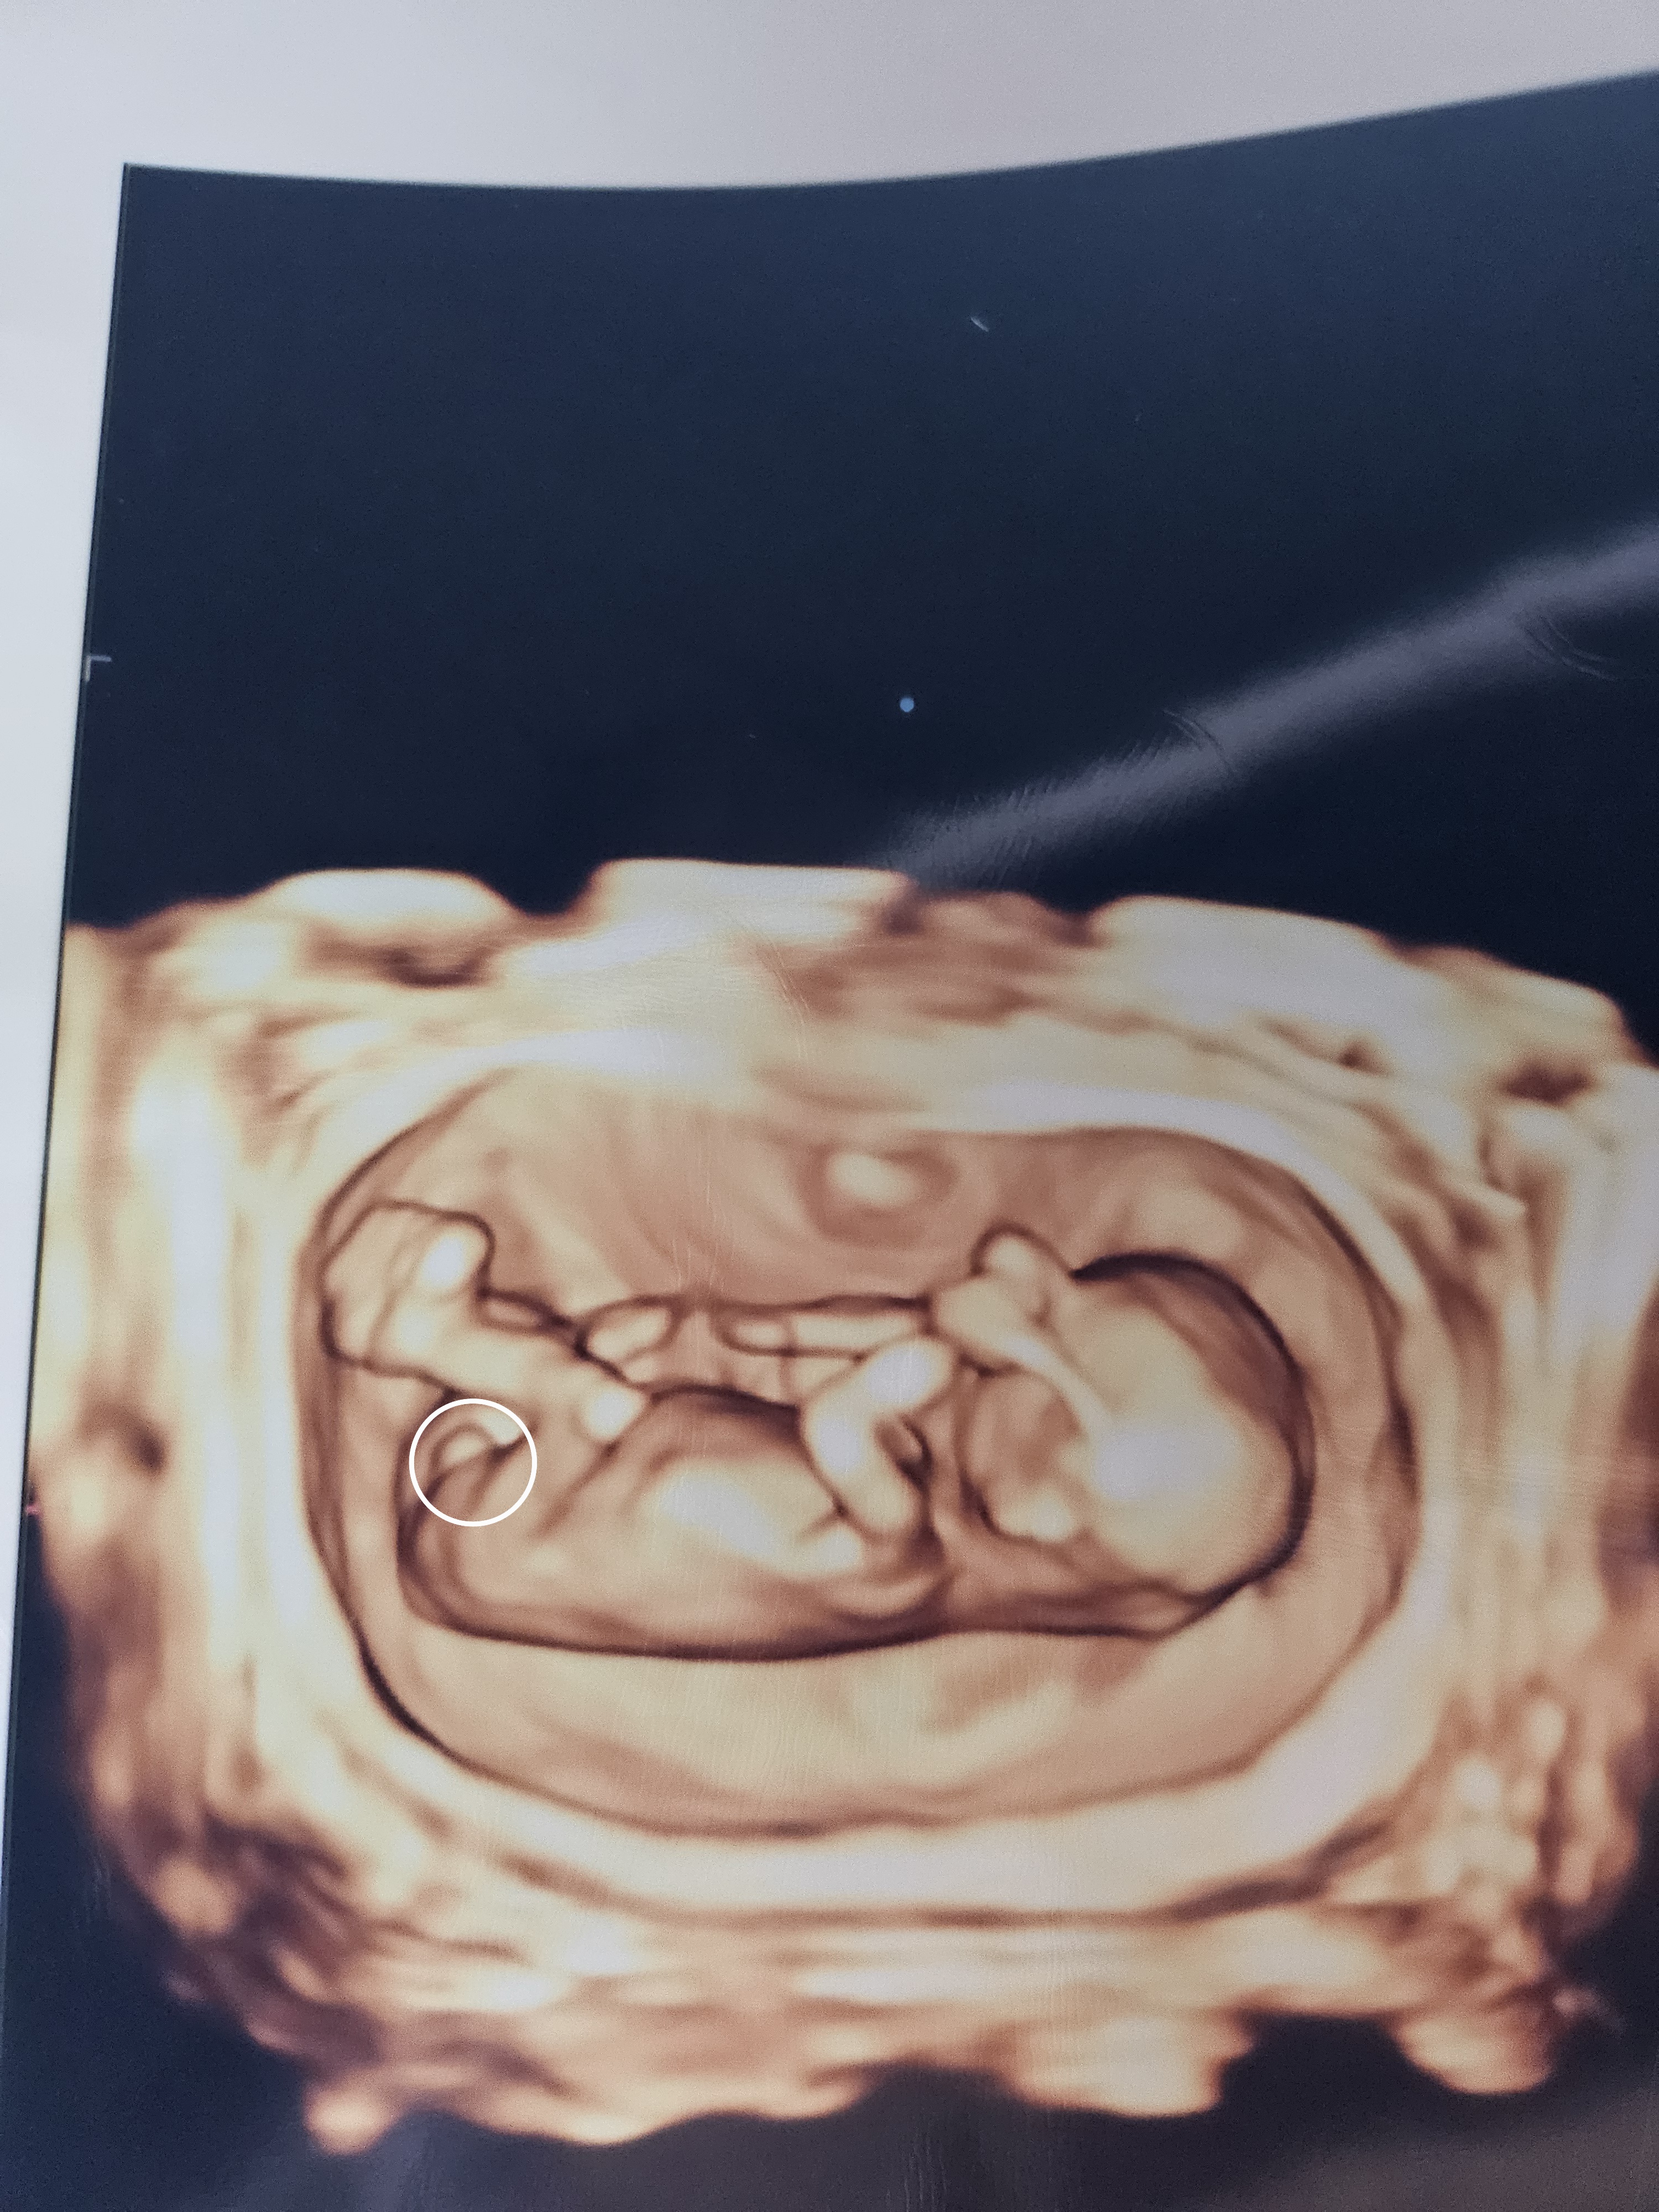

몸이 안좋아 오늘 서브병원갔다가 촘파보고왔어요!! 임신주수는 13주6일차인데 아가가 안커서 아가는12주5일 크기라고하셧는데 뭔가보인데요ㅋㅋ 서브병원이라 저장된 동영상은없고 입체촘파사진 하나뿐이라 올려봅니다 이 모양이면 확정일까요?ㅠ 16주까지 기다리기 넘힘드네용